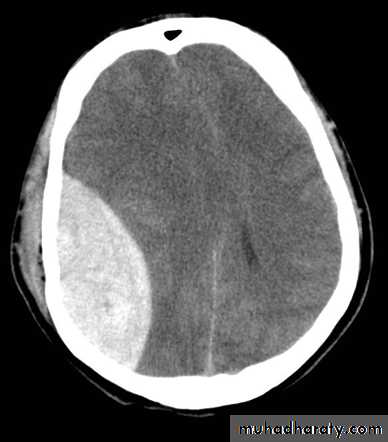

A. Extradural Hematoma:

Classically consist of a clot in the extradural space (between the bone and dura), biconvex in shape usually in the temporal area from bleeding of the middle meningeal artery (branch of maxillary artery) or its branches.25% of cases develop in other areas of brain as the frontal, parietal or posterior fossa.

CT scan or MRI.On CT scan there'll be a hyperdense biconvex extradural lesion.